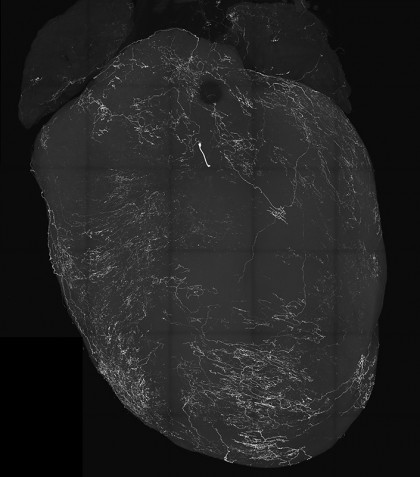

foto: O imagine a unei inimi marcată de neuronii senzoriali vagali. Într-un nou studiu publicat în revista Nature, cercetătorii de la UC San Diego È™i colegii lor au descoperit că aceÈ™ti neuroni declanÈ™ează leÈ™inul, punând o bază pentru abordarea tulburărilor legate de leÈ™in. Credit: Augustine Lab, UC San Diego